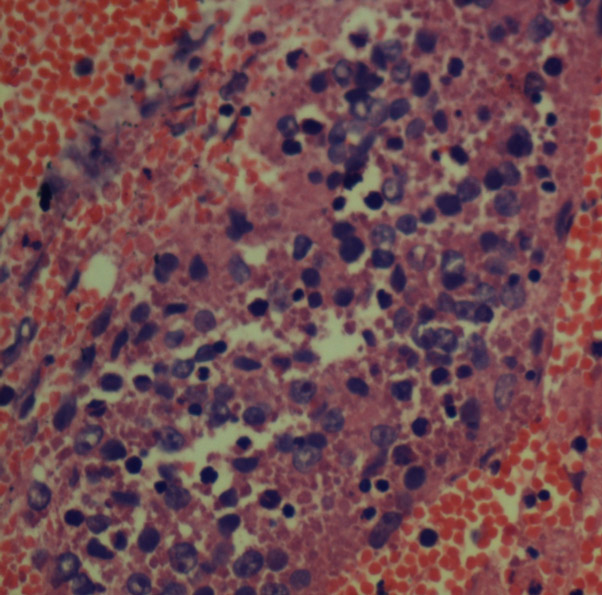

Hodgkins Lymphoma

Polymorphous cell polpulation MGG